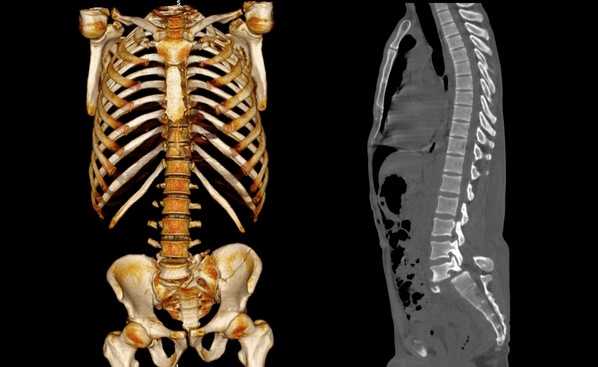

Трехмерная реконструкция при КТ

В результате компьютерной томографии получают серию послойных изображений рассматриваемой зоны. Монохромные фотографии обладают высоким разрешением. В отличие от рентгенографии на снимках отсутствуют дефекты и тени от расположенных рядом структур. Изменение плоскости при реконструкции изображений позволяет тщательно изучить анатомические образования. Преимуществом КТ является возможность создания 3D-модели позвоночника.

Компьютерная томография позвоночника показывает малейшие нарушения строения и функциональности суставных элементов. Трехмерное изображение при подготовке к хирургическому вмешательству позволяет локализовать патологический процесс, уточнить объем предстоящей операции.